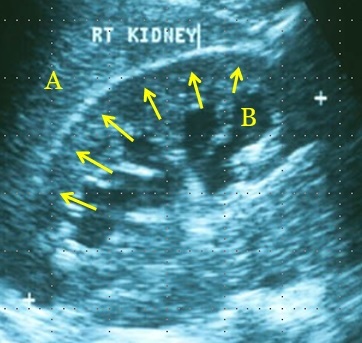

Name A, B and the arrows.

A - right lobe of the liver.

B - dilated calyx.

C - renal cortex.